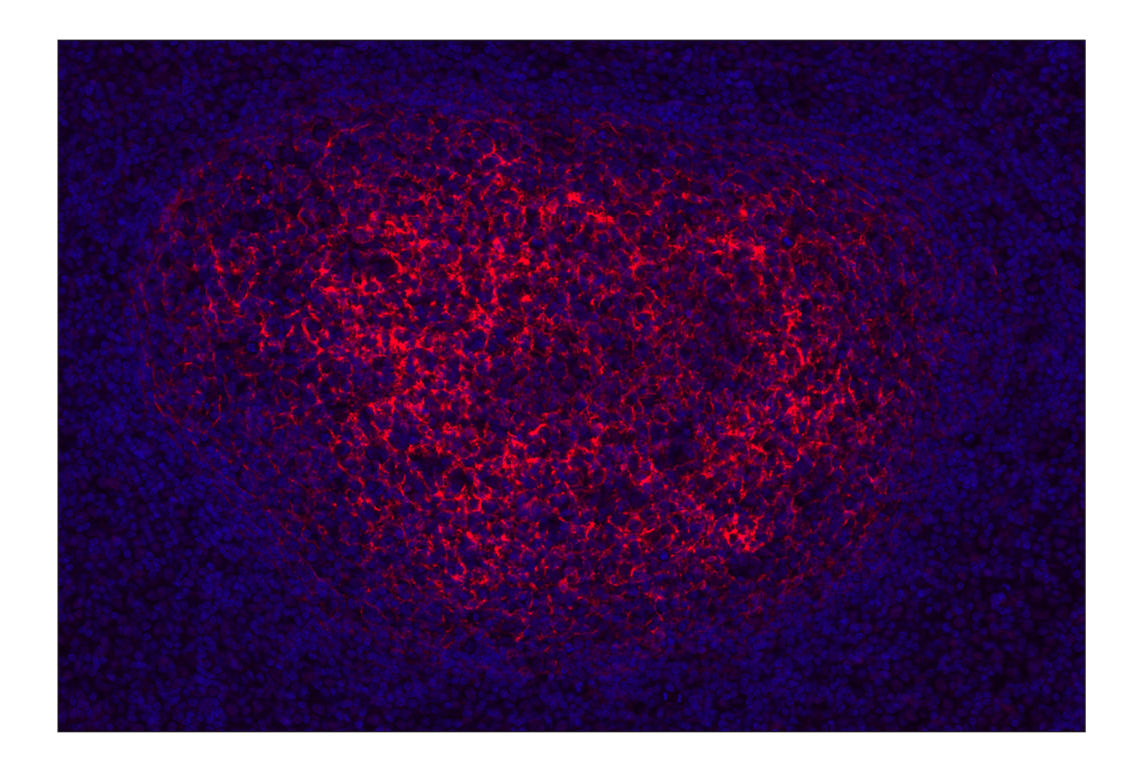

CR1/CD35 (E8B1Z) Rabbit Monoclonal Antibody (Alexa Fluor® 647 Conjugate) #17519

Immunohistochemistry (Paraffin) 1:50 - 1:200

CR1/CD35 (E8B1Z) Rabbit Monoclonal Antibody (Alexa Fluor® 647 Conjugate) recognizes endogenous levels of total CR1/CD35 protein. Non-specific staining was observed in skeletal muscle by immunohistochemistry.